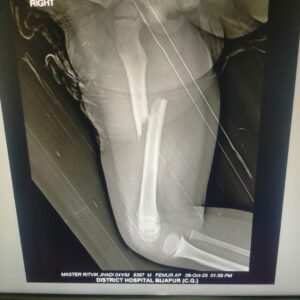

घबराएं पिता पोटा केबिन पहुंचने के बाद पता चला की वहीं की स्टाफ अनुदेशक लता मामडीकर घायल बच्चे को स्कूटी से अस्पताल लेकर पहुंचे । यहां जांच के बाद एक्सरे रिपोर्ट में पता चला मासूम बच्चे का पैर कमर और घुटने के बीच पूरी तरह टूट गया । दो भागों में विभाजित हो गया यह दृश्य को देख मां-बाप का रो-रोकर बूरा हाल । बेहतर उपचार के लिए दूसरे दिन 09 अक्टूबर 2025 को तेलंगाना भद्राचलम जागृति हॉस्पिटल ले गए ।